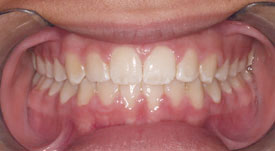

Crossbite

Crowding Front

Crowding Lower

Crowding Upper

Midlines

Narrow Upper Arch

Openbite

Overbite Front

Overbite Side

Protrusion

Spacing

Underbite